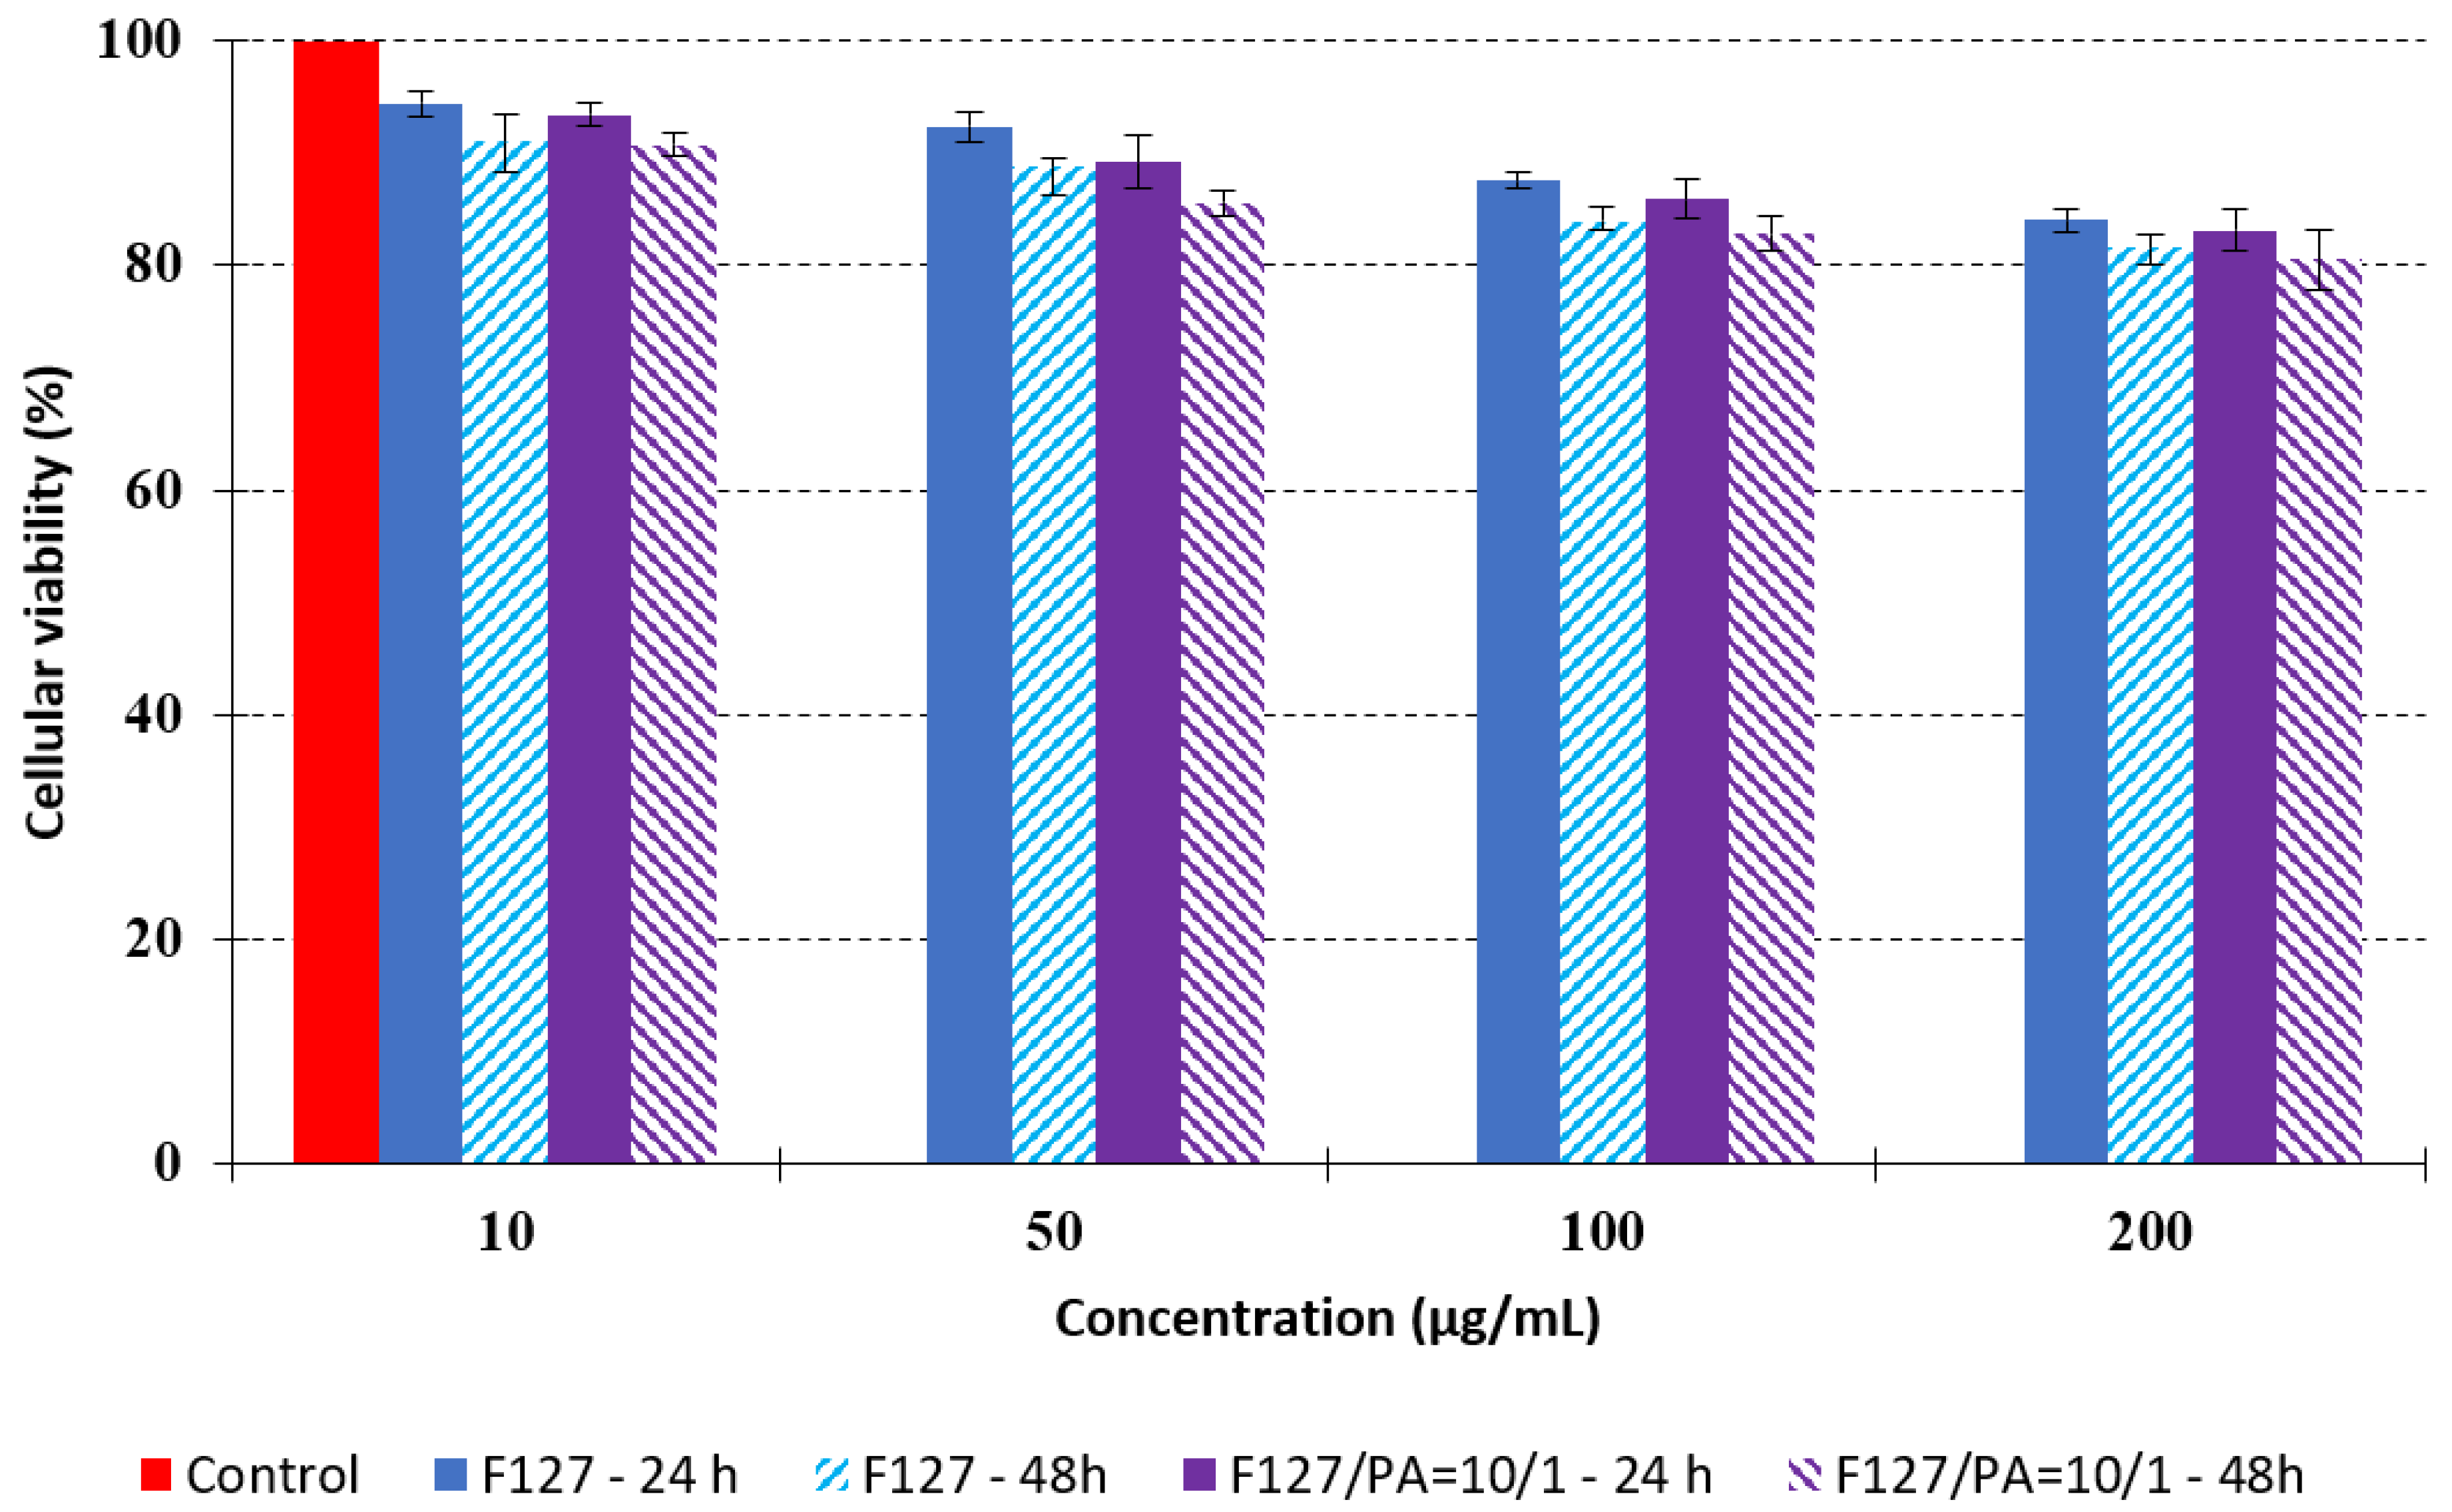

3.4. In Vitro Cytotoxicity Analysis